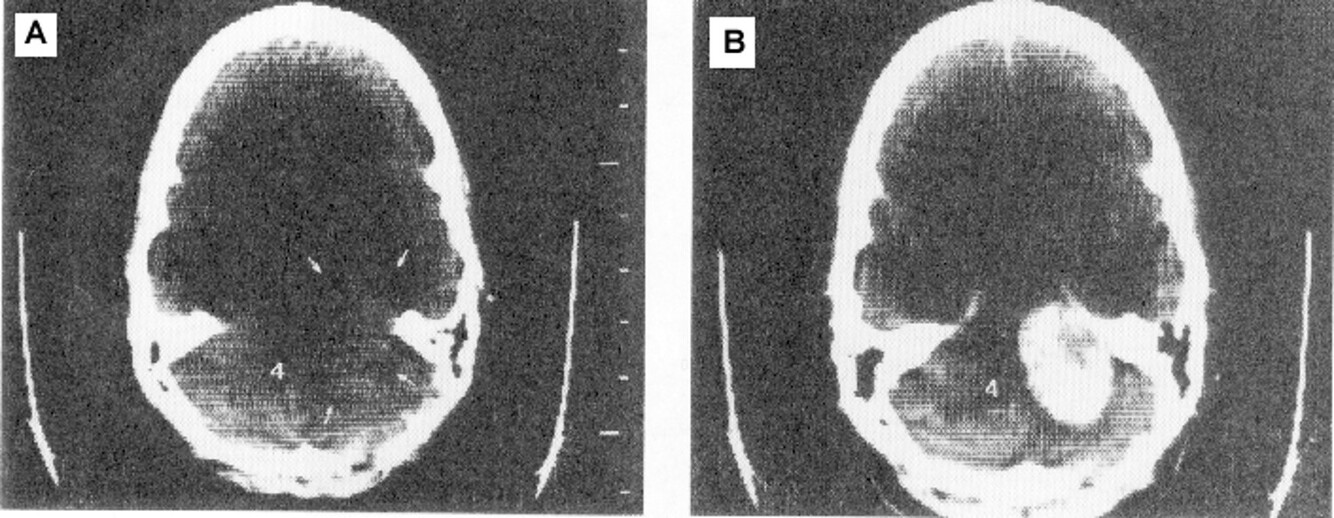

How does CT scan work?

Scanning with focused beam on thin layer of tissue. Show image according to absorption, Reconstruction by computer software

CT scan provides high _____________________ and is best for _____________________ and shows ______________

CT scan provides high spatial resolution and is best for bony structures and shows soft tissue better.

In CT scan, the contrast across different soft tissue is _____ as compared with MRI

low